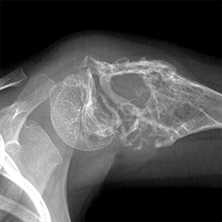

Какие кости поражаются при раке

Принципиально возможно развитие метастаза в любой кости скелета, но чаще всего опухолевые клетки задерживаются в костях с лучшим кровоснабжением, где всегда есть достаточное питание для продолжения неуправляемого деления. Очень редко метастазы образуются в мелких косточках кисти и стопы, но часты в обильно пронизанных сосудистой сетью костях таза, позвонках и ребрах, нередко поражают кости черепа, за исключением лицевого скелета. Наибольшую опасность для пациента несёт опухолевое поражение позвонков и трубчатых костей конечностей, когда в месте деструкции при обычной нагрузке случается перелом, лишающий возможности двигаться, а при патологическом переломе шейного позвонка высока вероятность паралича из-за сдавления спинного мозга отломками разрушенной опухолью кости.

- Далее по частоте следуют метастазы в костях таза — почти половина всех случаев, типичные локализации — подвздошная и лонные кости.

- Вполовину реже отмечается метастазирование в костях черепа и нижней конечности, где превалирует поражение бедренной кости.